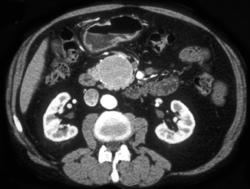

Diagnosis

Serous Cystadenoma